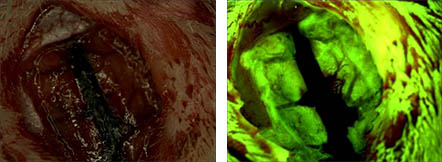

荧光:对样品做荧光标记来进行观察,主要做物质鉴定,如抗体、抗原、荧光原位杂交(FISH)等

— 荧光 —

— FISH研究 —

荧光原位杂交技术(fluorescence in situ hybridization),简称FISH,是利用荧光标记的特异核酸探针与细胞内相应的靶DNA分子或RNA分子杂交,通过在荧光显微镜下观察荧光信号,来确定与特异探针杂交后被染色的细胞或细胞器的形态和分布,或者是结合了荧光探针的DNA区域或RNA分子在染色体或其他细胞器中的定位。